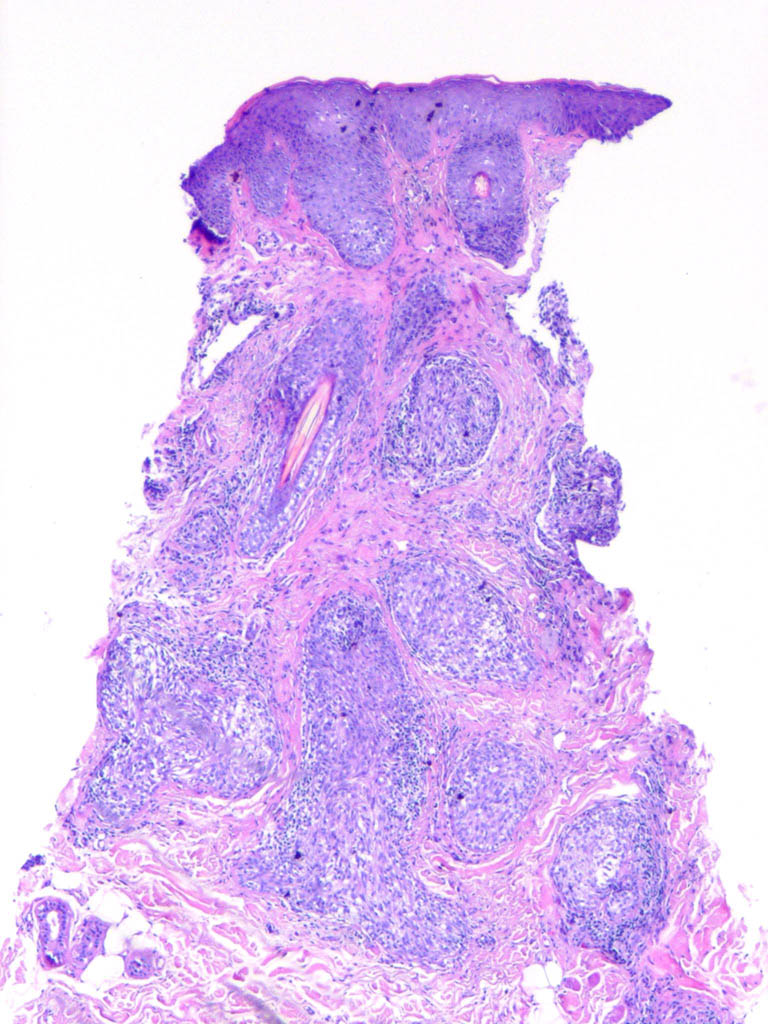

Cutaneous lymphadenoma =الغدوم اللمفاوي الجلدي